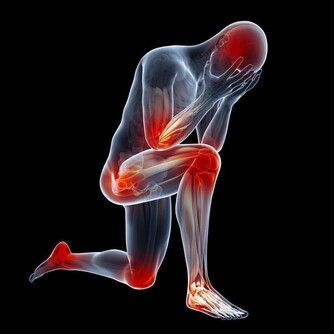

腎臟不好的8個信號

腰痛

腎臟位於腰部的脊柱兩側,因此當腎臟出現問題時,常會感到腰痛。